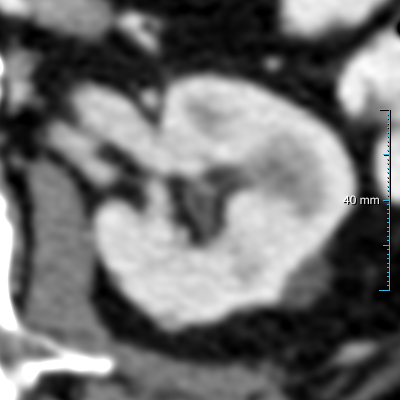

Case 1 (0.971 Dice) best from dataset B20subscript𝐵20B_{20}

Case 2 (0.950 Dice) median from dataset B20subscript𝐵20B_{20}

Case 3 (0.966 Dice) best from dataset B30subscript𝐵30B_{30}

Case 4 (0.953 Dice) median from dataset B30subscript𝐵30B_{30}

(a) Input slice

(b) Contours

Refer to caption

Figure 9: Comparison of four cases between experiment 1  , the reference standard, and the second observer on the test set B30 in annotation format 1. (a) shows the original slice and (b) shows the final predictions (red contours) of experiment 1  , the reference standard (green contours), and the second human observer (yellow contours). All the slices have a window center of 60 HU and a window width of 360 HU.